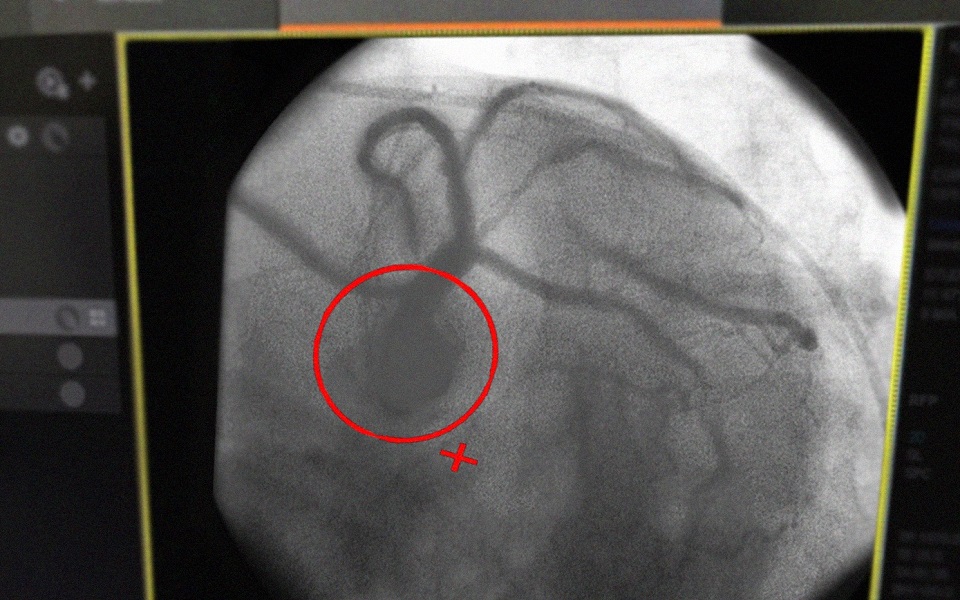

Прохожие вызвали бригаду скорой помощи, которая доставила мужчину в больницу, где диагностировали инфаркт. Пациенту провели операцию по установке стента.

Иллюстрации:  Минздрав Рязанской области